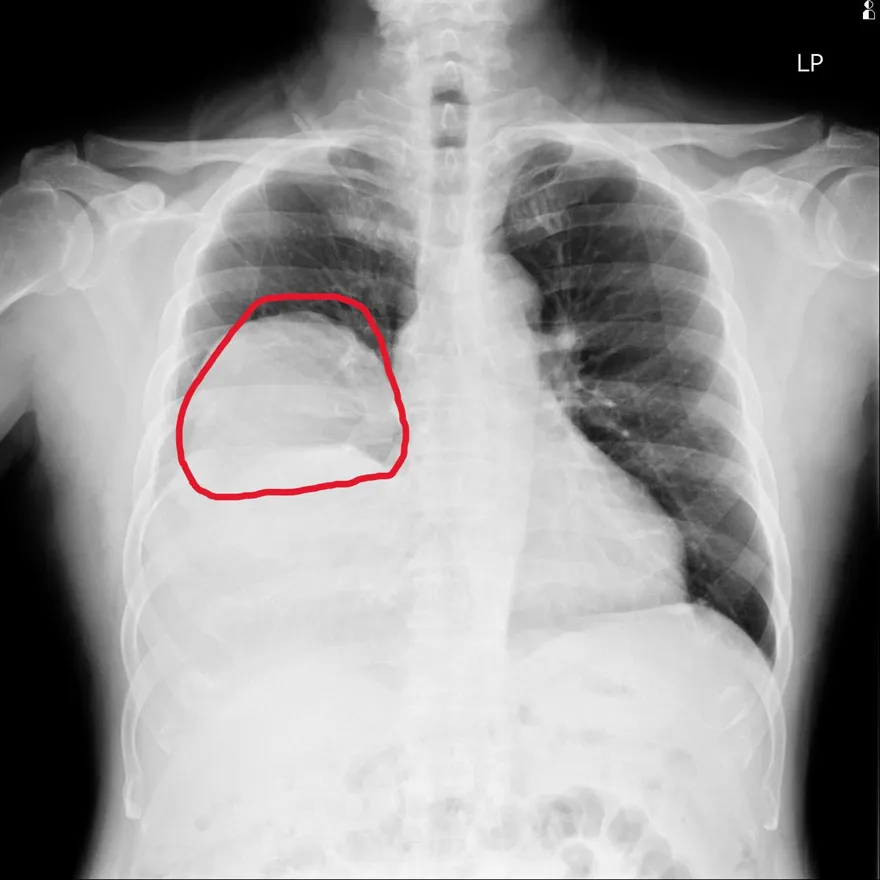

肺部腫瘤

肺部單發性纖維瘤

IGF-2腫瘤

腫瘤伴隨症候群

罕見肺腫瘤